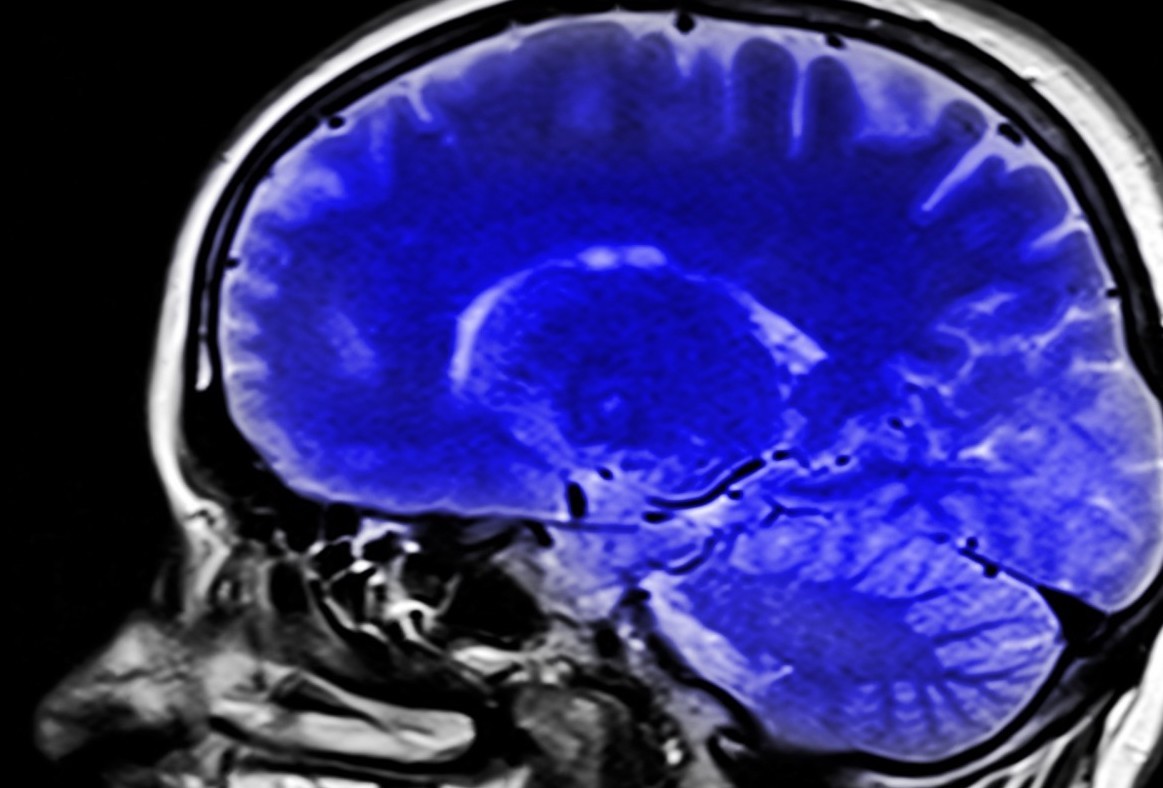

Un estudio realizado por el Centro Médico Irving de la Universidad de Columbia, en Estados Unidos, ha descubierto variantes genéticas raras asociadas a la esquizofrenia. La investigación, publicada en la revista ‘PNAS’, se realizó a partir de un grupo de 112 pacientes con esquizofrenia severa y muy resistente al tratamiento que han requerido una hospitalización prolongada en centros del Estado de Nueva York. Los resultados mostraron que más del 48% presentaba una variante dañina rara. Este hallazgo podría conducir a una mejor comprensión del pronóstico y la resistencia al tratamiento contra la esquizofrenia, así como generar mejores oportunidades de asesoramiento genético para las familias afectadas, según afirma Anthony Zoghbi, director del estudio.